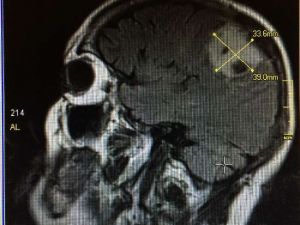

Konuşurken Beynindeki Tümör Alındı